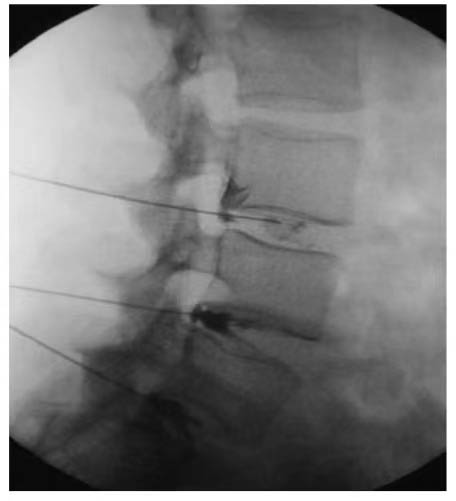

CT-Guided Spinal Injection: Precise Healing, New Hope

Our expert team has pioneered CT-guided spinal injection technology, designed specifically for stem cell therapy in the treatment of spinal cord injuries. During the procedure, real-time CT imaging generates dynamic 3D visuals of the spine, allowing surgeons to rotate and analyze the fracture site in multidimensional space. Through healthy anatomical pathways, the needle is carefully advanced, avoiding bony obstacles. As the surgeon guides the needle toward the spinal cord, the system continuously updates imaging to verify the trajectory angle and spatial relationship between the spinal cord and vertebrae, ensuring absolute precision and safety. This technology is often combined with lumbar puncture or intravenous stem cell therapy to enhance efficacy.